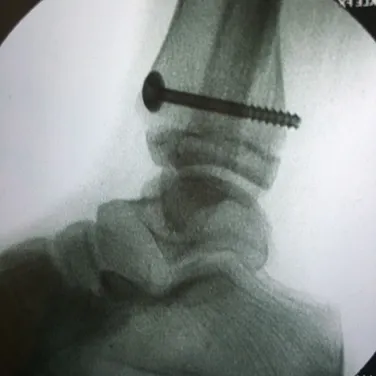

Nerves may be compressed from tight ligaments, inflamed tendons, tumors, fracture fragments, varicose veins, scar tissue or injuries to the foot that cause the foot and ankle to be misshapen (severe flatfoot).  Nerve compression may cause significant discomfort with weightbearing.  Night pain and pain while the patient is nonweightbearing are common as well.  The most important a physician can do is to direct the treatment to the cause of the problem.  If the foot is misshapen causing no pain (numbness, tingling or shooting), the nerve does not need surgery, the foot and ankle bones might.  The wrong diagnosis can be disastrous.  If a tumor or varicose vein is causing the pain they may need to be resected to allow the nerve to function normally.  Anything abnormally applying pressure to the nerve may cause symptoms.  If a tight ligament is identified, it has to be released to allow the nerve to function normally.  Occasionally nerve conduction studies are performed to assess the degree of nerve compression and nerve damage. The common peroneal nerve is located at the fibular neck, just to the outside of the knee.  If the nerve is injured or damaged, it can cause a dropfoot due to paralysis of the muscles that it innervates.

Nerves may be compressed from tight ligaments, inflamed tendons, tumors, fracture fragments, varicose veins, scar tissue or injuries to the foot that cause the foot and ankle to be misshapen (severe flatfoot).  Nerve compression may cause significant discomfort with weightbearing.  Night pain and pain while the patient is nonweightbearing are common as well.  The most important a physician can do is to direct the treatment to the cause of the problem.  If the foot is misshapen causing no pain (numbness, tingling or shooting), the nerve does not need surgery, the foot and ankle bones might.  The wrong diagnosis can be disastrous.  If a tumor or varicose vein is causing the pain they may need to be resected to allow the nerve to function normally.  Anything abnormally applying pressure to the nerve may cause symptoms.  If a tight ligament is identified, it has to be released to allow the nerve to function normally.  Occasionally nerve conduction studies are performed to assess the degree of nerve compression and nerve damage. The common peroneal nerve is located at the fibular neck, just to the outside of the knee.  If the nerve is injured or damaged, it can cause a dropfoot due to paralysis of the muscles that it innervates.  Nerves may be compressed from tight ligaments, inflamed tendons, tumors, fracture fragments, varicose veins, scar tissue or injuries to the foot that cause the foot and ankle to be misshapen (severe flatfoot).  Nerve compression may cause significant discomfort with weightbearing.  Night pain and pain while the patient is nonweightbearing are common as well.  The most important a physician can do is to direct the treatment to the cause of the problem.  If the foot is misshapen causing no pain (numbness, tingling or shooting), the nerve does not need surgery, the foot and ankle bones might.  The wrong diagnosis can be disastrous.  If a tumor or varicose vein is causing the pain they may need to be resected to allow the nerve to function normally.  Anything abnormally applying pressure to the nerve may cause symptoms.  If a tight ligament is identified, it has to be released to allow the nerve to function normally.  Occasionally nerve conduction studies are performed to assess the degree of nerve compression and nerve damage. The common peroneal nerve is located at the fibular neck, just to the outside of the knee.  If the nerve is injured or damaged, it can cause a dropfoot due to paralysis of the muscles that it innervates.